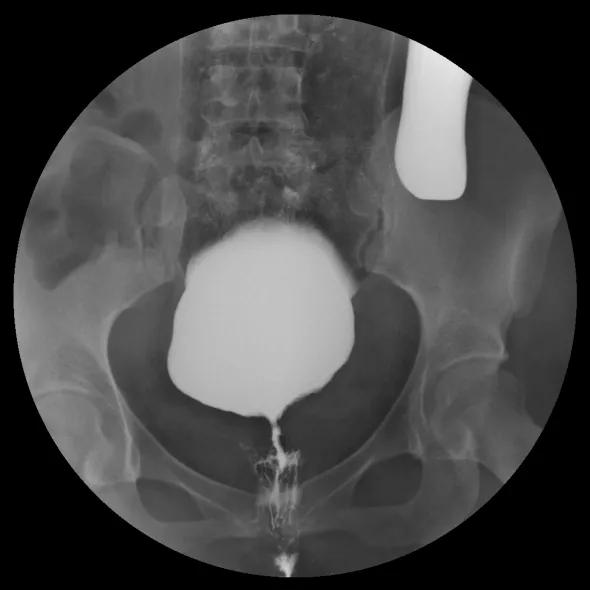

△直肠远端前壁→阴道内可见造影剂显示

小静不仅 直肠阴道瘘复发 了

还存在 巨结肠和乙状结肠冗长症